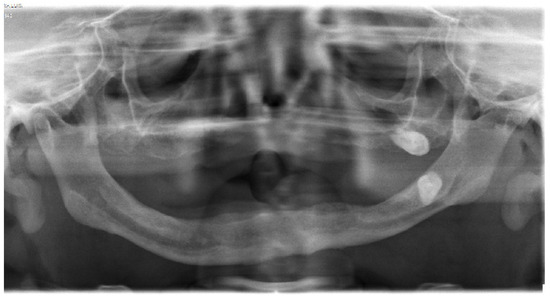

8. Maxilofacial Features

In 2011, the patient herself sought treatment as she had a complete loss of teeth and an extreme maxillary atrophy. She requested surgical intervention for the implant of teeth. However, an orthopantomography confirmed the high degree of atrophy, describing very fine alveolar edges and type IV maxillomandibular atrophy. Due to the state of the jaw bones, the surgical intervention was not considered (Figure 5).

Figure 5.

Orthopantomography of patient.